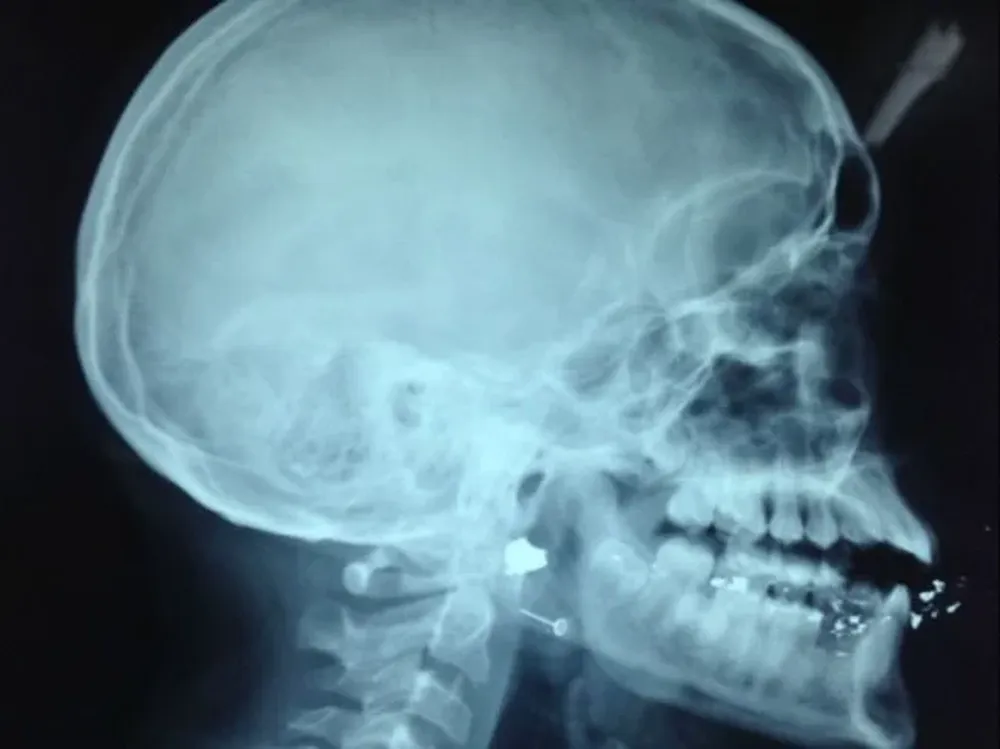

Para los pediatras —en especial para los emergencistas, intensivistas y cirujanos— la coyuntura les implica un aprendizaje. Porque en el mundo criminal no hay balas pediátricas. Los proyectiles se diseñan para matar, a la mayor cantidad posible, con la mayor eficacia posible, en el menor tiempo posible. Y esa lógica, en el pequeño cuerpo de un niño, hace estragos.

"Es frecuente que veamos tatuajes de entrada (como les dicen los cirujanos al orificio de ingreso de la bala al cuerpo) de una forma, pero un tatuaje de salida bien diferente por todo lo que la fuerza cinética de las balas causaron al romper tejidos", señaló el cirujano Kierszenbaum. No solo eso:

"Un niño pierde sangre a la misma velocidad que un adulto, pero como su cuerpo tiene mucho menos sangre (es un envase más chico, para decirlo en criollo) las chances de desangrarse son mucho mayores".